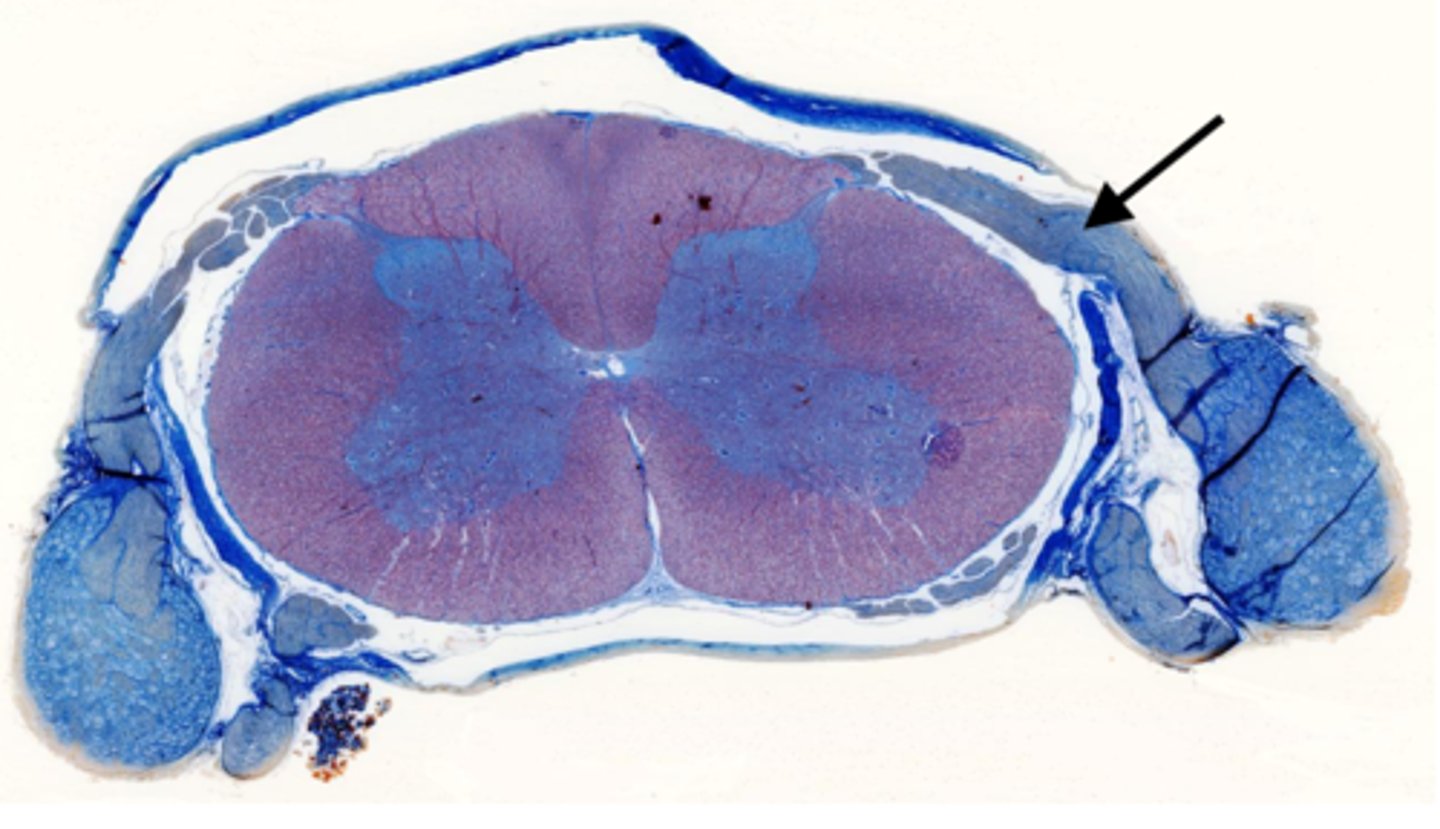

Identify the part of the spinal cord

dorsal funiculi

lateral funiculi

ventral funiculi

dorsal horn

ventral horn

dorsal root of spinal nerve

ventral root of spinal nerve

Identify the section of the spinal cord that contains nuclei

gray matter

Identify the section of the spinal cord that contains nerve tracts

white matter

central canal

Identify the part of the meninges

pia mater

arachnoid

dura mater

dorsal root ganglion